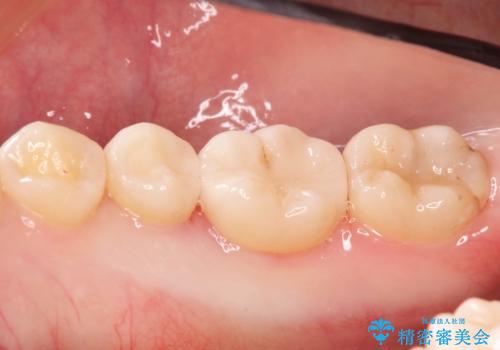

自然な見た目のセラミックインレー

- むし歯の治療を希望されて来院された患者様です。

セラミックインレーによる修復を行っております。

自然な見た目に満足して頂きました。